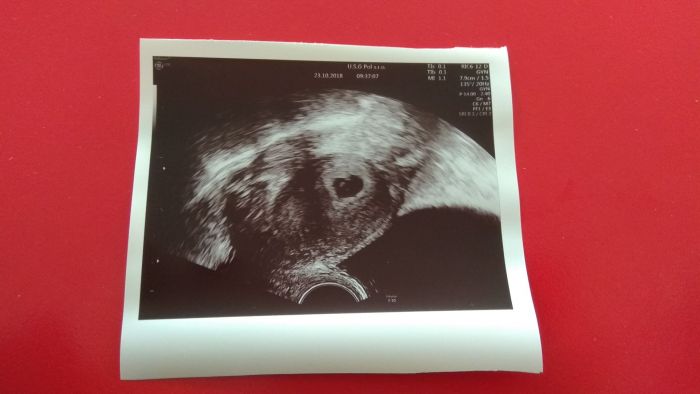

A už mate u nějaké foto z UTZ?

Ahoj holky, tak my už máme první fotečku

podle menstruace bychom měli být 8tt a TP kolem 10.června, ale prcek je ještě malinký, takže podle něj to ještě nešlo změřit.